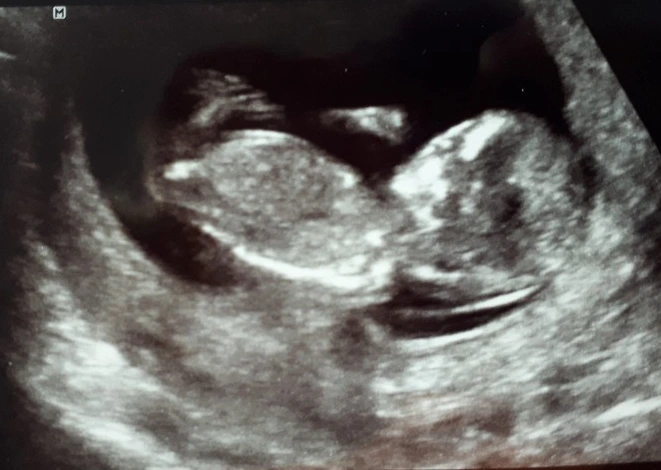

배 위를 유영하듯 무언가를 찾던 선생님의 손이 한 곳을 향해 자리를 잡았다. 이내 사람의 모양을 한 조그만 무언가가 눈에 들어왔다.

"아가기 잘 자리 잡고 있네요. 여기 얼굴이고요, 손, 발.."

첫 검사치고는 꽤 시간이 지나서 온 터라 아이는 어느 정도 자라 있는 상태였다. 그렇게 사람의 형태를 하고 있을 거라고는 생각하지 못했는데 손과 발이 다 나있는 모습이 그저 신기했다. 선생님이 말씀하신 아이의 크기를 가늠해 보니 아직 정말 작은 생명체였다. 머리로 있다고만 여기고 몸으로 느끼기는 했지만 실체를 보지는 못했던 아이의 존재를 우리는 처음 눈으로 만나고 있었다.

뱃속에서 꼬무닥꼬무닥 살아 움직이는 아이의 모습을 보는데 신기하게 어떤 기운이 차올랐다.

앞으로 남편의 일이 어떻게 될지, 비싼 병원비를 감당하며 자연출산을 할 수 있을지, 아이를 잘 키울 수 있을지 대한 고민들이 순간 다 사라지는 듯했다.

내 뱃속에서 꼬물거리는 아이가 아직 세상에 나오지도 않은 아이가 나에게 의지와 용기를 불어넣고 있는 것이었다.

생명이 주는 에너지! 나는 그것을 느꼈다.

"와~ 저렇게 손발이 다 있을 줄은 몰랐네. 진짜 신기하다."

"그지? 나도 이만큼 컸을 줄은 몰랐는데, 근데 아이 보고 나니 왠지 기운이 나는 것 같아."

"어, 나도! 어떤 마음이 들까 궁금했는데 보고 있으니 막 힘이 솟는 것 같더라고."